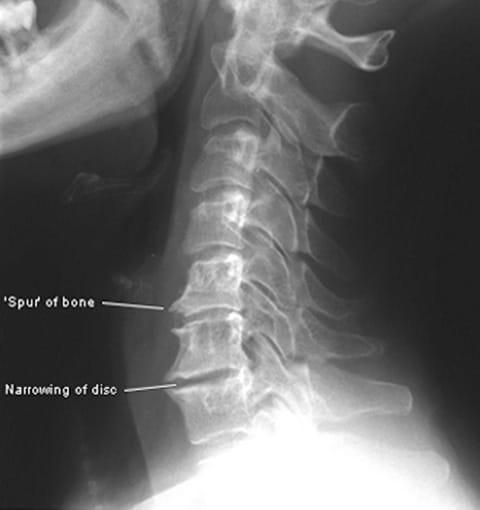

Vertebrogenic Headaches are caused by problems with the vertebrae in the cervical spine. These headaches may be felt in the back, sides and front of the head or in the front of the face or neck. Chronic irritation of the nerve roots between the vertebrae can be caused by changes to the normal curvature of the cervical spine caused by trauma, degenerative arthritis or poor posture.

The onset of pain is often acute and may also cause muscle contractions in the neck that can often trigger tension headaches as well. Pain is the body’s way of alerting us that something is wrong. It is unwise to ignore these signals and treat just the symptoms.